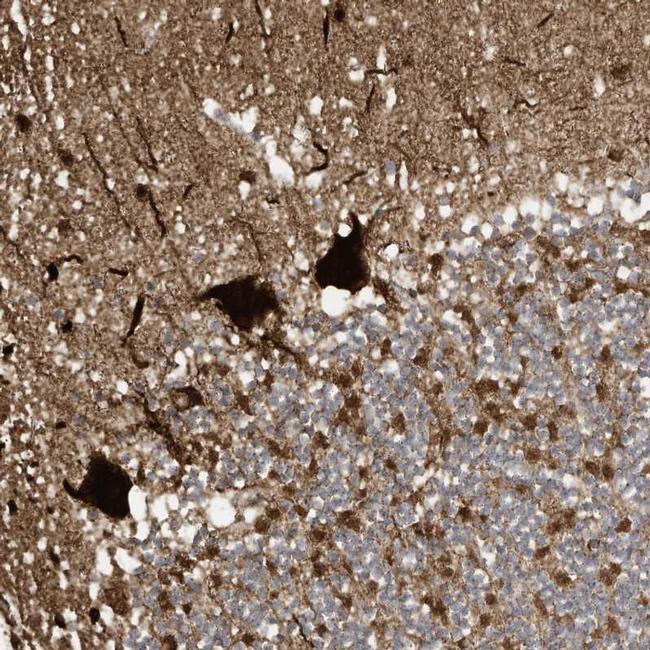

- Main image

- Experimental details

- Immunohistochemical staining of MROH9 in human cerebellum tissue shows strong cytoplasmic positivity in Purkinje cells. Samples were probed using a MROH9 Polyclonal Antibody (Product # PA5-55843).